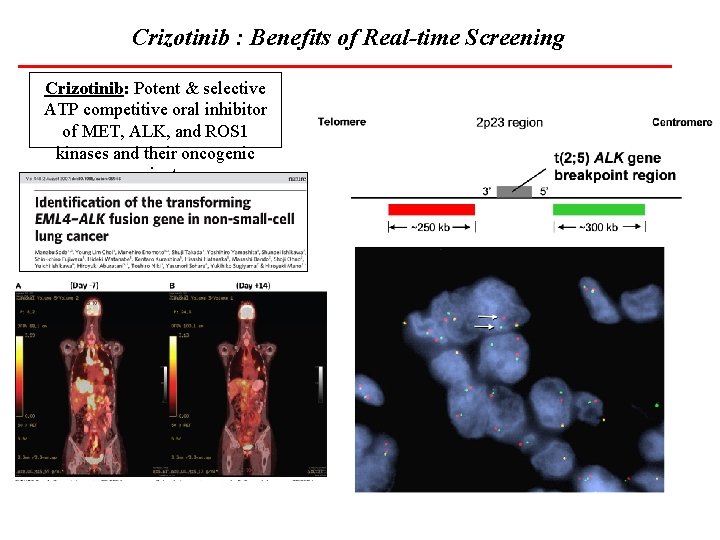

Crizotinib : Benefits of Real-time Screening Crizotinib: Potent & selective ATP competitive oral inhibitor of MET, ALK, and ROS 1 kinases and their oncogenic variants